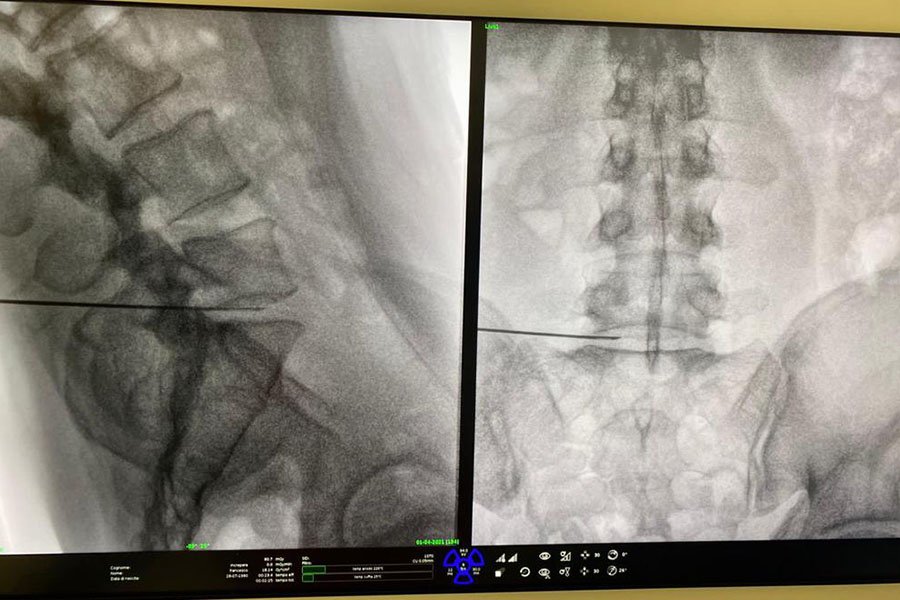

- Nucleolisi discale con ozono: prevede l’iniezione, in anestesia locale e sotto controllo radiologico, di ozono medicale all’interno del disco vertebrale da trattare